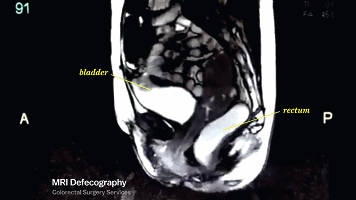

而膀胱和直肠,也会因为肌肉的收缩反应开始颤抖。

这也是为什么啪啪啪有时候会使你出现尿急感的原因。

(左:膀胱;右:直肠)